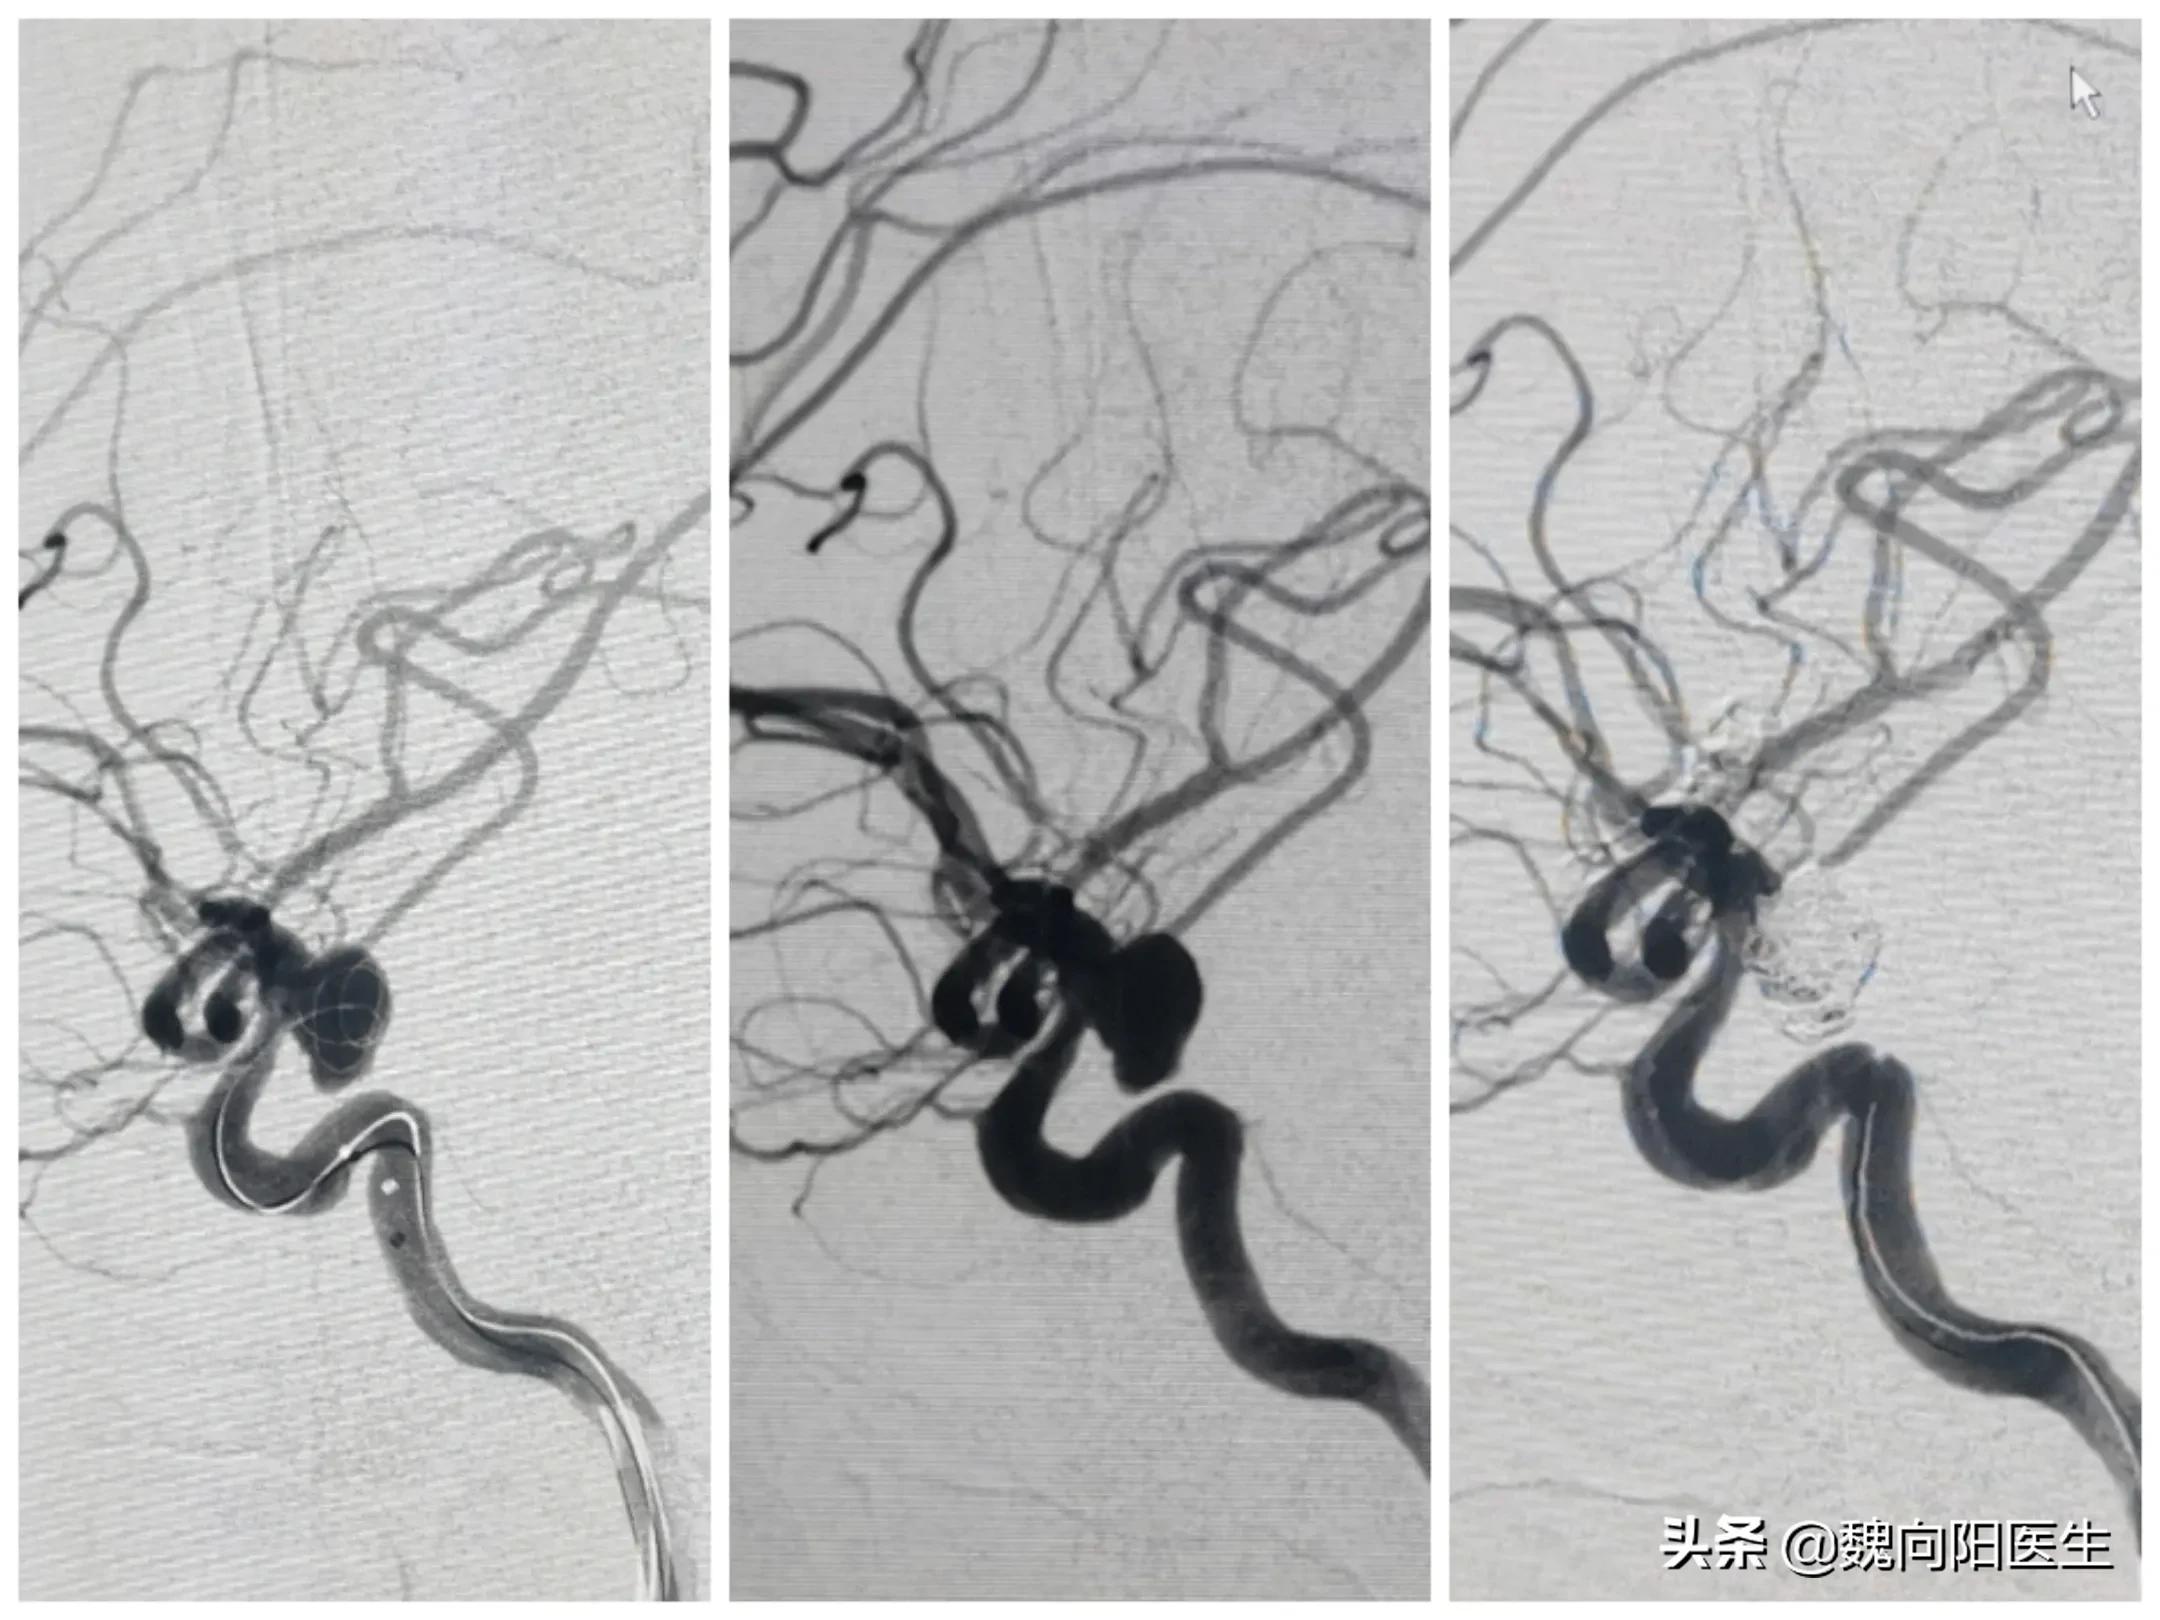

当送至我院后,再次复查头CT发现:“患者蛛网膜下腔出血较前增多,伴双侧侧脑室扩大”,且患者和昏迷状态更加严重,出现了呼吸困难情况,在急诊立即给予经口气管插管术,给予呼吸机辅助通气治疗。患者目前的意识状态逐渐加重,考虑是患者急性蛛网膜下腔出血并发急性脑积水导致,且脑积水情况进行性加重,立即给予侧脑室穿刺引流,改善脑室积水。诊断周某是自发性蛛网膜下腔出血,不排除患者出血原因是颅内动脉瘤破裂导致,因此建议立即行脑血管造影检查,明确发病原因,并给予有针对性的治疗。经患者家属同意后,立即联系介入导管室,给予全麻下脑血管造影发现:“小脑后下动脉动脉瘤”,经过分析考虑该动脉瘤为责任病灶,如果不处理该动脉瘤,则第二次出血风险高,且一旦再次出血后症状会更加严重,甚至危及生命。

再次与患者家属沟通后,给予经导管颅内动脉瘤栓塞治疗。

动脉瘤栓塞